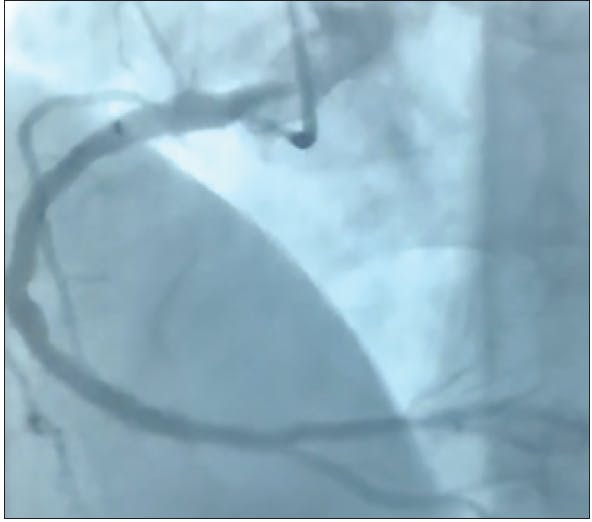

INTERVENTION

Ultrasound-guided access was obtained through the right femoral vein. A 65-cm 8-F Destination sheath (Terumo Interventional Systems) was advanced into the right pulmonary artery, first over a telescoping balloon tip catheter and stiff angle Glidewire® (Terumo Interventional Systems). Because the patient was not a candidate for thrombolysis, the decision was made to intervene with the Indigo System CAT8XTORQ115 and SEP 8, which were advanced sequentially into the right then left pulmonary artery. Using the usual telescoping technique of the sheath, the CAT8 and SEP8 were used in tandem to aspirate the thrombus using sustained aspiration with Penumbra ENGINE.

There was an immediate response in the clinical situation of the patient: her blood pressure stabilized into the 90s and her oxygenation improved substantially. Pulmonary artery peak pressures dropped from the mid 40s to the high 30s. Angiograms showed pre- and postthrombectomy of the right pulmonary artery with modest clot debulking but significant improvement in right lung perfusion. Within 72 hours, repeat echocardiography showed RV/LV ratio improvement from 1.43 to 0.98. The patient had a robust recovery and was discharged to her rehab facility on anticoagulation.

DISCUSSION

In patients with submassive pulmonary embolism with compromised right ventricular function and elevated biomarkers, the Indigo System is an excellent frontline tool offering a safe and effective1 treatment option. The Indigo System can provide immediate mechanical relief by extracting clot while decreasing pressures using sustained power aspiration without the need for thrombolytics. This is potentially more effective than diminished syringe-based aspiration. The low-profile catheter and Penumbra ENGINE are easy to set up and use. The procedure can be performed quickly,1 which is important for symptomatic patients.